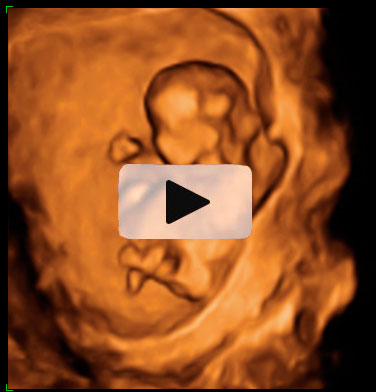

El movimiento de gemelos en el útero encierra sorpresas, como en esta ecografía 4D en la que vemos a dos hermanos en sus respectivas bolsas. El gemelo de la derecha parece estar bailando el "hula hoop" con su propio cordón umbilical, que le rodea las piernas formando un círculo. Destaca la posición casi erguida del niño dentro del útero materno, casi a punto de dar un paso. Cuando uno de los fetos genera mucho movimiento, suele arrastrar a su gemelo a que se mueva también, aunque esté adormecido.

Ecografía 4D de gemelos de 12 semanas moviéndose: el baile del "hula hoop"